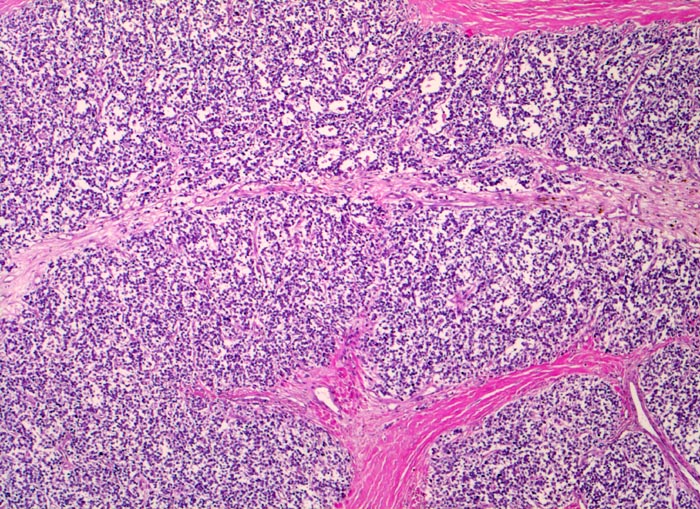

• Durch Bindegewebssepten abgegrenzte Knoten (lobuläre Architektur).

• Blauer, klein- und rundzelliger Tumor.

• Uniforme Zellen mit schmalem, kaum abgrenzbarem Zytoplasmasaum und unscharfen Zellgrenzen. Rundliche oder ovale Zellkerne mit leicht vergröbertem Chromatin und punktförmigen kleinen Nukleolen.

• Quetschartefakte (gequetschte Zellen sind dunkler und haben verkleinerte abgeflachte Zellkerne).

Die Tumoren sind makroskopisch grauweiss und wachsen destruktiv und infiltrativ. Nekrosen und Einblutungen sind häufig. Histologisch lassen sich solide Rasen monomorpher, kleiner, rundlicher Tumorzellen mit dichtem Chromatin und wenig Zytoplasma nachweisen (sog. small-blue-round cells). Metastasen treten vor allem in der Lunge und in anderen Skelettabschnitten auf. Die Differentialdiagnose klein-blau- und rundzelliger Tumoren im Kindesalter ist breit. Kleinzellige Osteosarkome, Neuroblastome, Lymphome und mesenchymale Chondrosarkome können ein histologisch ähnliches Bild zeigen, speziell in kleinen Biopsien, und müssen mit Hilfe von (molekularen) Zusatzuntersuchungen und unter Einbezug klinischer und radiologischer Befunde voneinander abgegrenzt werden.